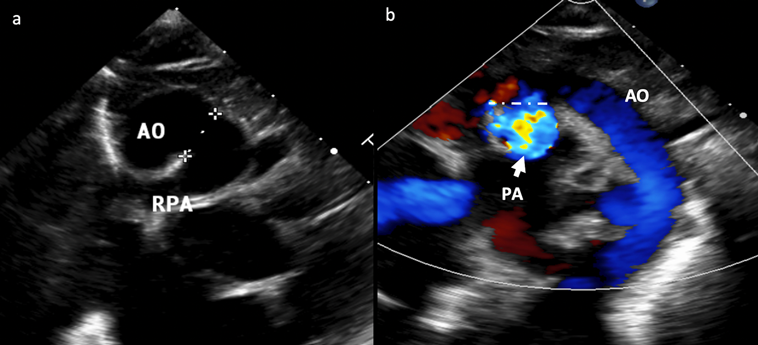

A full-term baby (male, birth weight 3.1 kg) was admitted with signs and symptoms of heart failure, but without cyanosis, at 10 days of life. His pulse oximeter indicated 96% on room air with respiratory rate 56/min, heart rate 147/min, blood pressure 69/35 mmHg. Chest X-ray showed plethoric lung fields and cardiomegaly (Fig. 1). Oxygen was given 1 L/min via a nasal cannula. Frusemide and spironolactone are started. His hemoglobin was 20.0 g/dL, hematocrit 58%, total white blood cells 13,600 µ/L, platelets 181,000 µ/L, CRP 0.1 mg/L, with normal renal function (urea 4.6 mmol/L, Na 133 mmol/L, K 4.5 mmol/L, Cl 95 mmol/L, Ca 2.35 mmol/L). An urgent 2D-Echo showed a large VSD, AP window (Fig. 2) and also PA sling suspected. Thoracic CT angiography confirmed Type 2a PA sling with severe tracheal stenosis. The so-called “tracheal bronchus” gave rise to the right upper lobe; its branching being as if at the usually expected location for the carina. The bifurcation to the right lower lobe and the left lung in this patient was present lower down with abnormal orientation (the bronchi more horizontally oriented than usual). The left PA is located at the T6–7 level just above the carina which resulted in distal airway stenosis (Fig. 3). The SVCs were bilateral structures. Lung volumes appeared fair bilaterally. The coronary arterial origins were normal. Cardiac MRI illustrated the right atrium and the right ventricle dilated, and also reconfirmed PA sling of the left PA as well as AP window between the distal AscAo and the right main PA (Supplementary Movie S1).

Fig. 2 a: 2D-Echo in a modified suprasternal view showing aortopulmonary window. b: 2D-Echo in a modified suprasternal view with colour Doppler. AO, aorta; PA, pulmonary artery; RPA, right pulmonary artery.